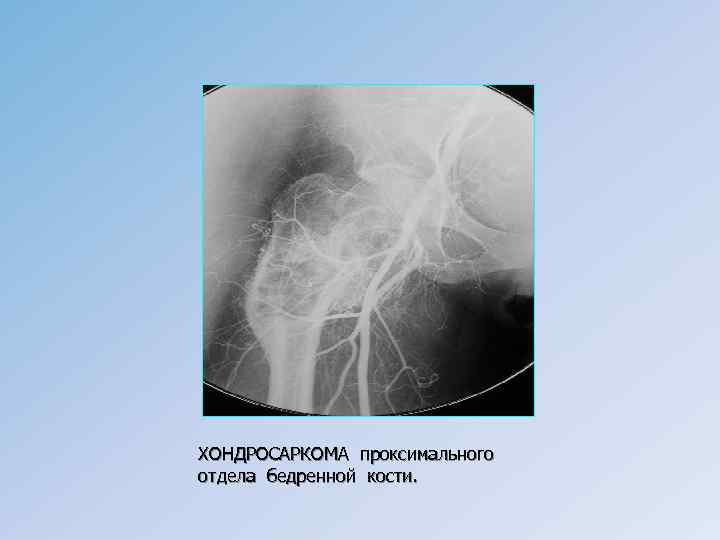

Злокачественные хрящеобразующие опухоли Хондросаркома может развиваться как первичная злокачественная опухоль и как вторичная в результате озлокачествления доброкачественной хрящевой опухоли или диспластического процесса. • Первичные хондросаркомы могут возникнуть в любой кости, развивающейся из хряща путем энхондрального окостенения, и отличаются широким диапазоном клинических проявлений – от местно деструктирующей опухоли до новообразования с выраженной злокачественной потенцией, что зависит от ее морфологического строения. Чем менее выражена анаплазия, тем более благоприятно протекает заболевание. • Клиническая картина характеризуется теми же признаками, что и при других первичных злокачественных опухолях костей (боли, опухоль, нарушение функции). Имеет значение локализация опухоли в кости. При центральной форме сначала появляются боли, опухоль как первый признак отмечается в основном при периферическом варианте.

• Рентгенологически центральные высокодифференцированные хондросаркомы проявляются в виде одиночного очага деструкции неправильной формы, кость вздута и утолщена, веретеновидно деформирована, сопровождается формированием ячеисто-трабекулярной структуры с наличием очагов обызвествления. При низкодифференцированных опухолях очаг деструкции имеет мелкоочаговый размытый характер, процесс распространяется на значительном протяжении по длинной оси кости. • Лечение зависит от формы хондросаркомы и в основном направлено на радикальное хирургическое удаление опухоли в пределах здоровых тканей. • Прогноз при радикальном лечении – процент 5 -летней выживаемости колеблется от 15 до 76, 4 %.

ХОНДРОСАРКОМА проксимального отдела бедренной кости.